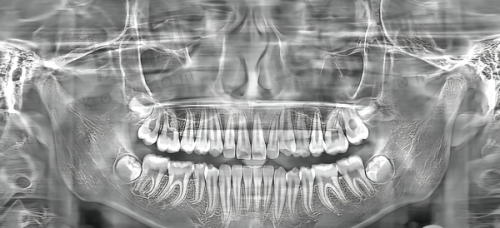

北京美冠塔口腔医院的口腔修复项目参考金额为3000元,预计修复时间为90天。在这个价格区间内,医院凭借其专精的医生团队和精良的技术,为患者提供高质量的口腔修复服务。医生们会根据患者的具体口腔状况,制定个性化的修复方案,确保修复成效达到至佳。而且医院使用的都是优质的材料,在确保修复成效的同时,也保护了患者的口腔健康。